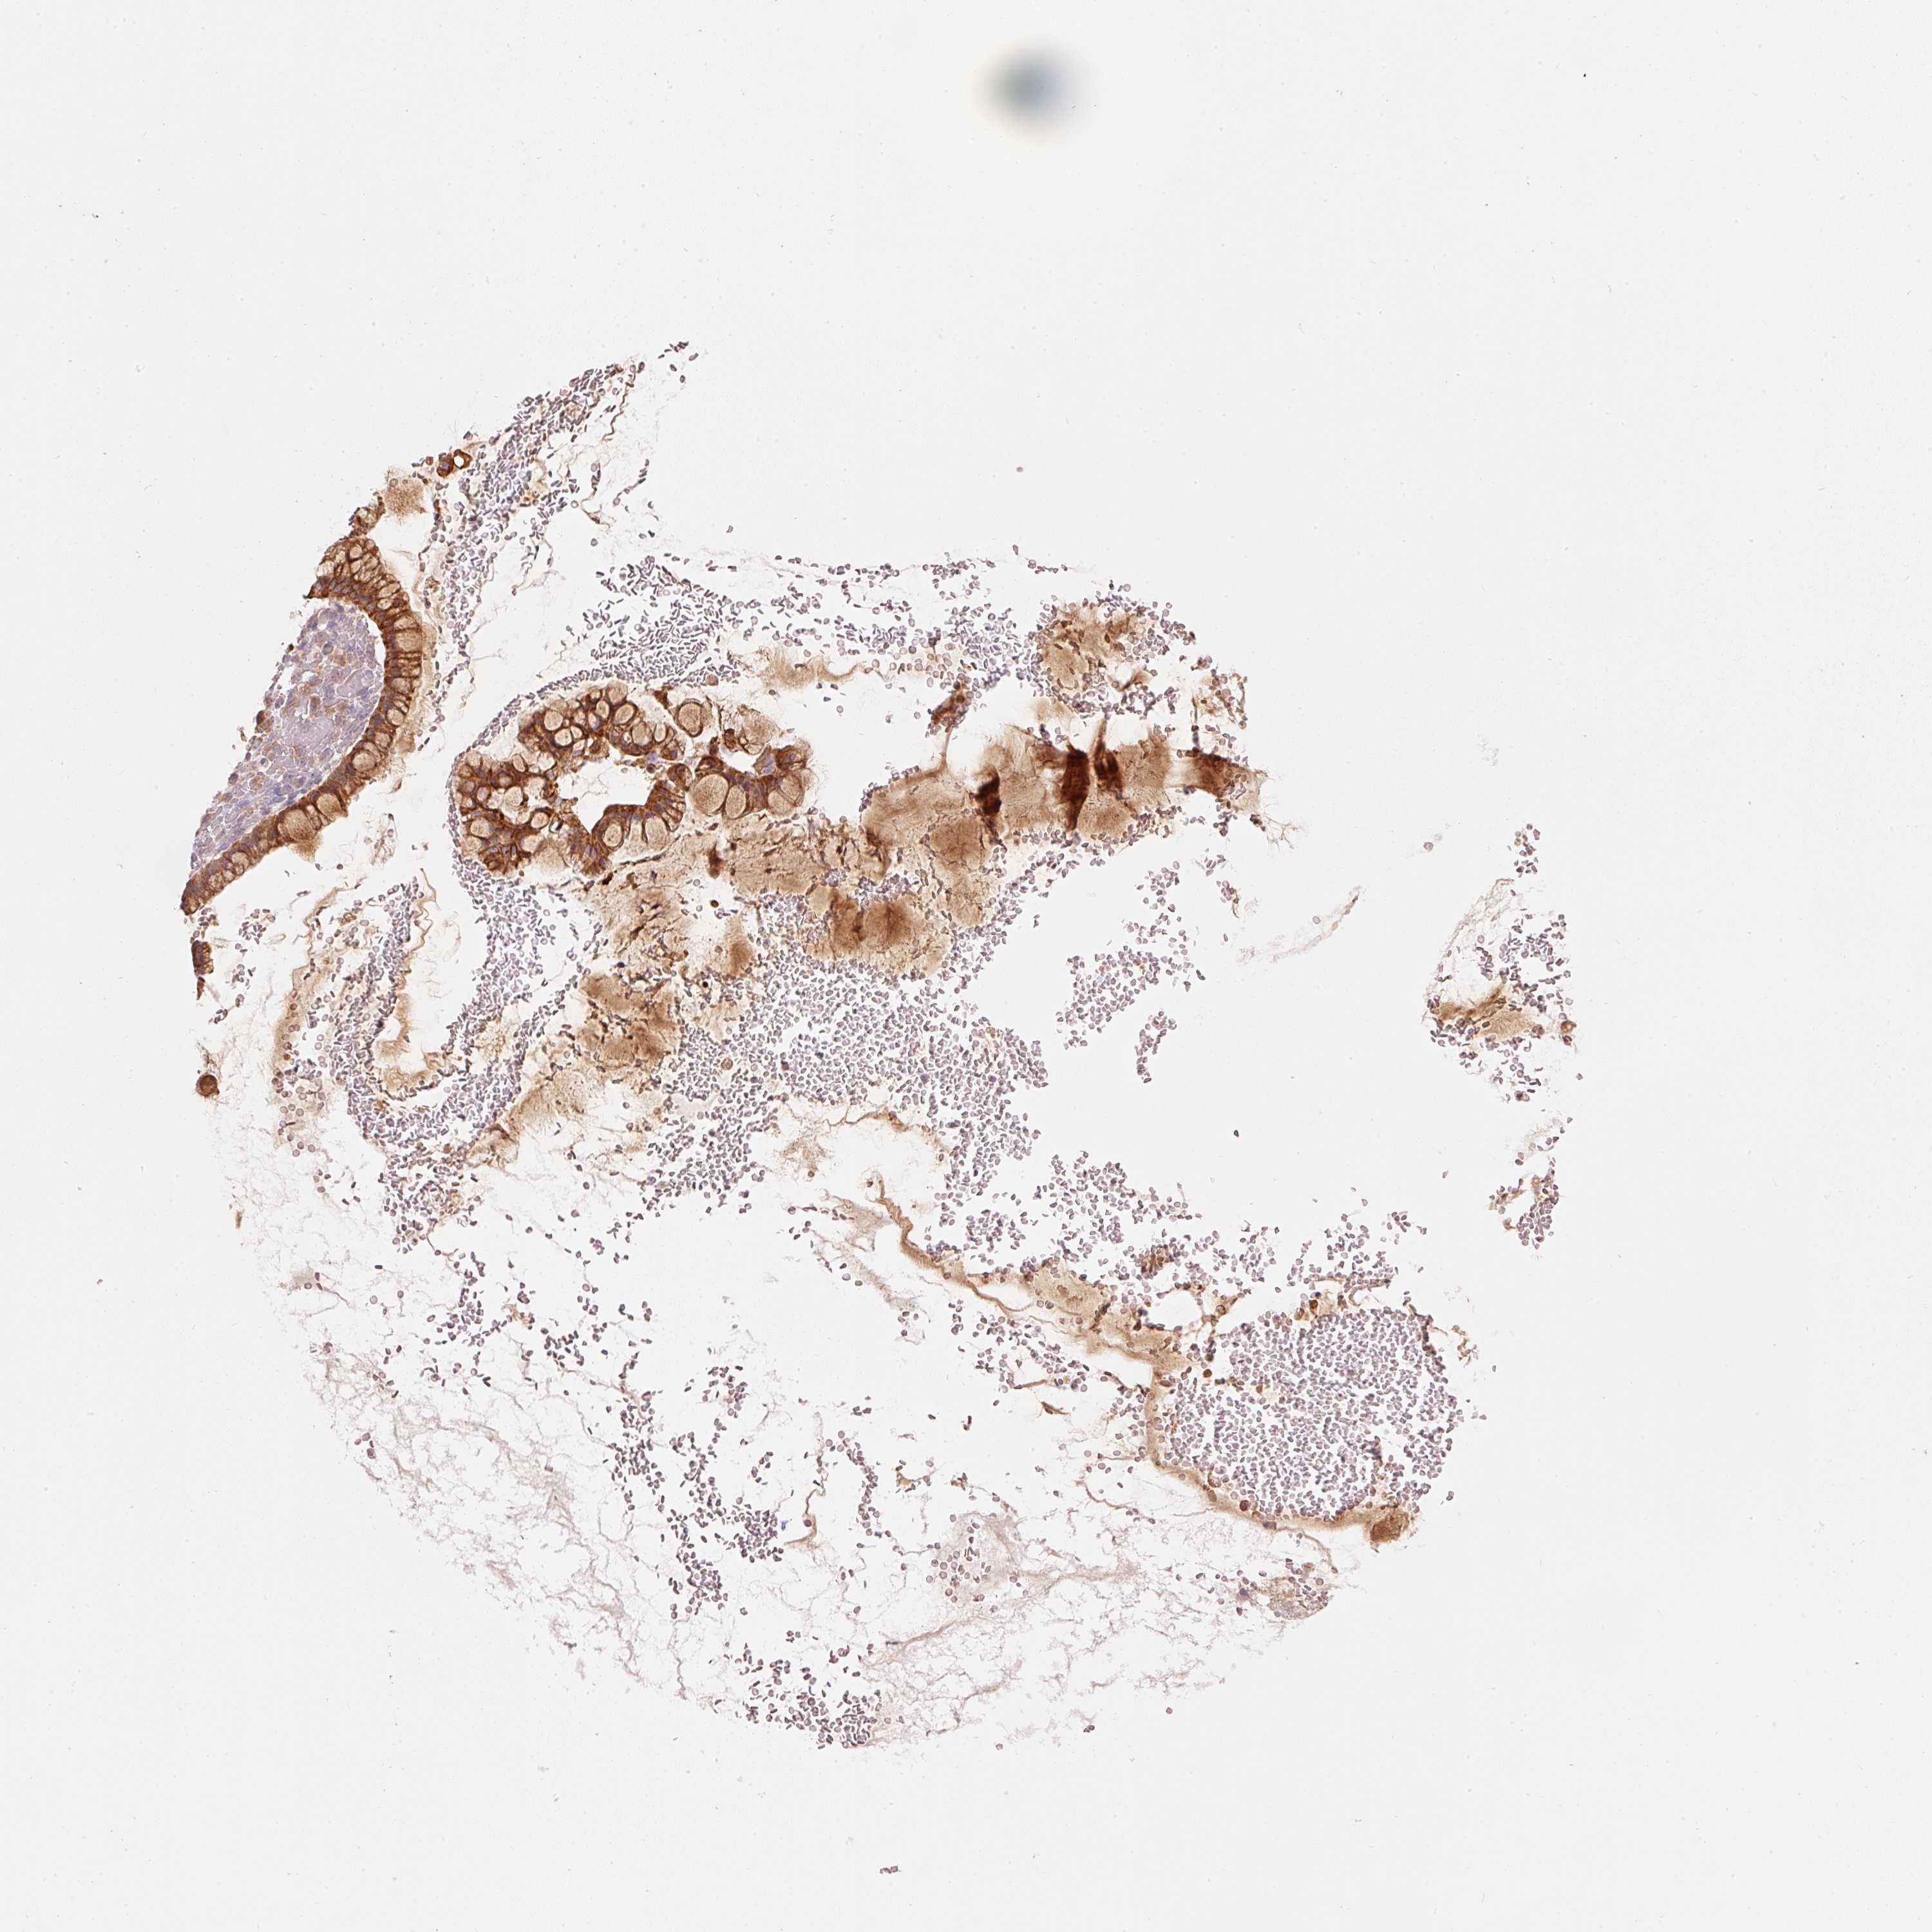

OVARIAN CANCER - Protein expressioni

A mouse-over function shows sample information and annotation data. Click on an image to view it in a full screen mode. Samples can be filtered based on level of antibody staining by selecting one or several of the following categories: high, medium, low and not detected. The assay and annotation is described here.

Note that samples used for immunohistochemistry by the Human Protein Atlas do not correspond to samples in the TCGA dataset.

Antibody stainingi

Antibody staining in the annotated cell types in the current human tissue is reported as not detected, low, medium, or high, based on conventional immunohistochemistry profiling in selected tissues. This score is based on the combination of the staining intensity and fraction of stained cells.

Each image is clickable and will lead to virtual microscopy that enables deeper exploration of all samples and also displays staining intensity scores, fraction scores and subcellular localization as well as patient and tissue information for each sample.

Antibody HPA052496

Staining

High

Medium

Low

Not detected

Intensity

Strong

Moderate

Weak

Negative

Quantity

>75%

75%-25%

<25%

None

Location

Nuclear

Cytoplasmic/membranous

Cytoplasmic/membranous,nuclear

Cystadenocarcinoma, serous, NOS

Carcinoma, endometroid

Cystadenocarcinoma, mucinous, NOS

Carcinoma, NOS